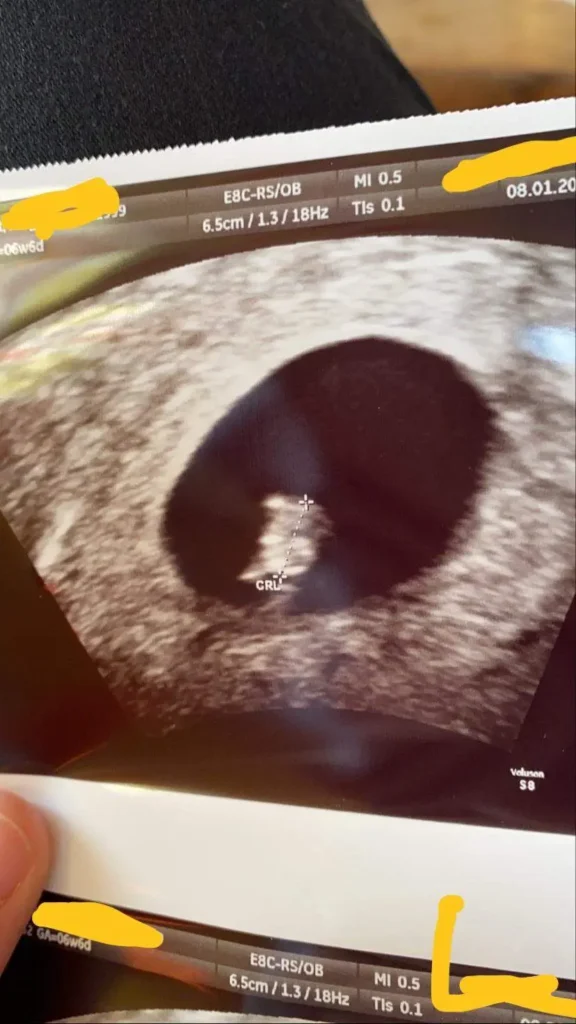

In der Schwangerschaftswoche sollte die Fruchthöhle einen Durchmesser von etwa 10-15 mm haben. In dieser Woche kann der Embryo bereits sichtbar sein und sollte etwa 3-5 mm groß sein. Der Dottersack, der dem Embryo Nährstoffe liefert, sollte außerhalb der Amnionhöhle liegen und einen Durchmesser von etwa 5 mm haben.

Die Größe der Fruchthöhle ist ein wichtiger Indikator für die Entwicklung des Embryos. In den ersten Wochen der Schwangerschaft wächst die Fruchthöhle sehr schnell, um Platz für das wachsende Baby zu schaffen. Die Größe der Fruchthöhle kann auch verwendet werden, um das Alter des Embryos zu schätzen.

Die Größe der Fruchthöhle wird mit einem Ultraschall gemessen. Der Arzt kann die Größe der Fruchthöhle anhand des Ultraschallbildes messen.